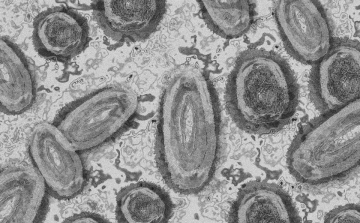

Tovább nőtt a majomhimlő-fertőzöttek száma Magyarországon

Újabb kilenc, 23-50 éves férfinél igazolták a majomhimlő-fertőzést Magyarországon, ezzel 42-re nőtt a fertőzöttek száma - közölte a Nemzeti Népegészségügyi Központ (NNK) csütörtökön az MTI-vel.